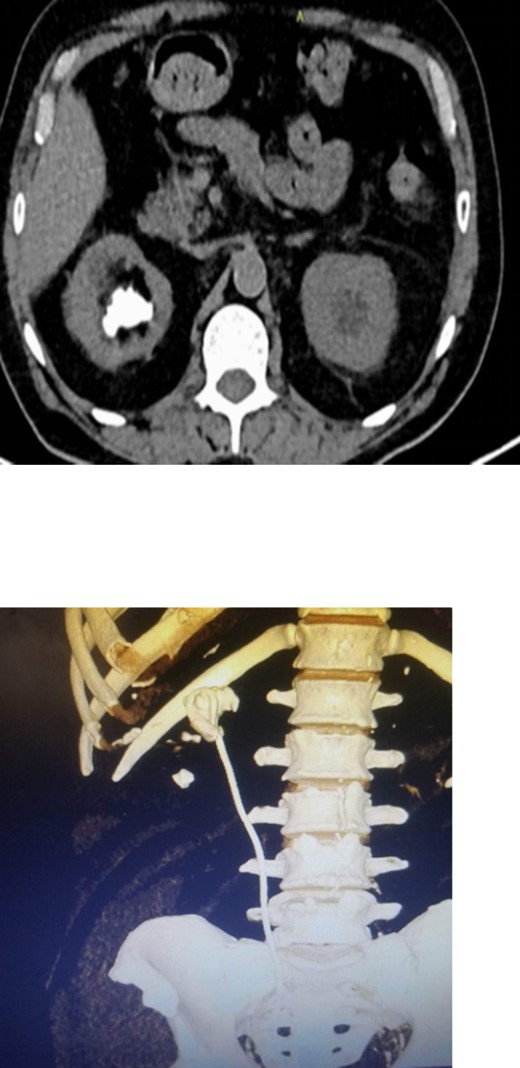

Postoperatively, a low dose non-contrast CT scan confirmed stone clearance (Fig. 6). Subsequent outpatient follow-up with renal ultrasound showed no residual hydronephrosis. The newly inserted double J stent was removed three weeks after the percutaneous nephrolithotomy procedure.

3D constructed image of postoperative low dose non-contrast CT scan showing stone clearance and newly inserted DJ stent in-situ.